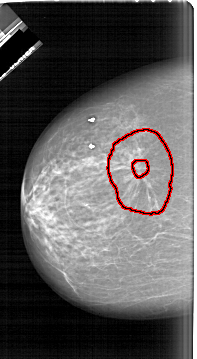

A_1628_1.LEFT_CC

LEFT_CC LINES 6451 PIXELS_PER_LINE 3541 BITS_PER_PIXEL 12 RESOLUTION 43.5 OVERLAY

FILE: A_1628_1.LEFT_CC.OVERLAY

TOTAL_ABNORMALITIES 1

ABNORMALITY 1

LESION_TYPE MASS SHAPE ARCHITECTURAL_DISTORTION MARGINS SPICULATED

ASSESSMENT 5

SUBTLETY 5

PATHOLOGY MALIGNANT

TOTAL_OUTLINES 2

BOUNDARY

CORE